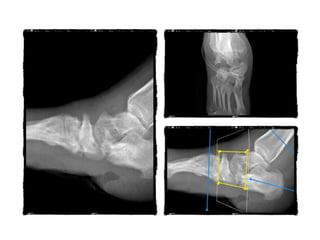

17.11.20 25.11.20

FOLLOW UP

25.01.21

18.03.2021

19.03.21

13.05.21

27.05.21